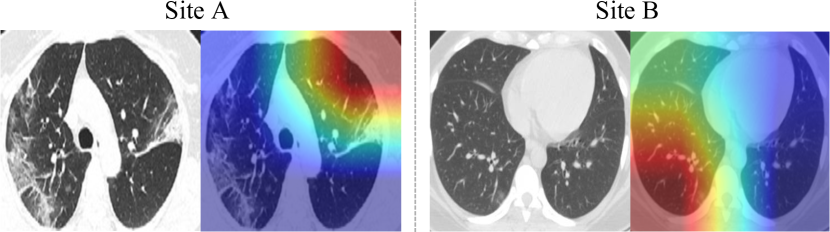

Refer to caption

Figure 4: Visualization of color maps using Grad-CAM [41].

Figure 5: Visualization of color maps of failure cases with Grad-CAM [41].

To understand the behavior of our framework, we observe the Grad-CAM [41] visualization results on the two heterogeneous sites, as saliency maps (shown in Figure 4). It is consistently observed on both datasets that the suspicious lesion regions are successfully localized across various abnormality patterns (e.g., bilateral and peripheral ground-glass, and consolidative pulmonary opacity), even with quite mild lesions. This analysis reveals promising interpretability of our classification model trained with image-level labels, demonstrating potential clinical relevance for COVID-19 image-based computer-assisted diagnosis. In addition, we present typical failure cases in Figure 5. We see that the method would mis-classify samples due to wrongly attended regions, and fail to distinguish images with unobvious lesions.